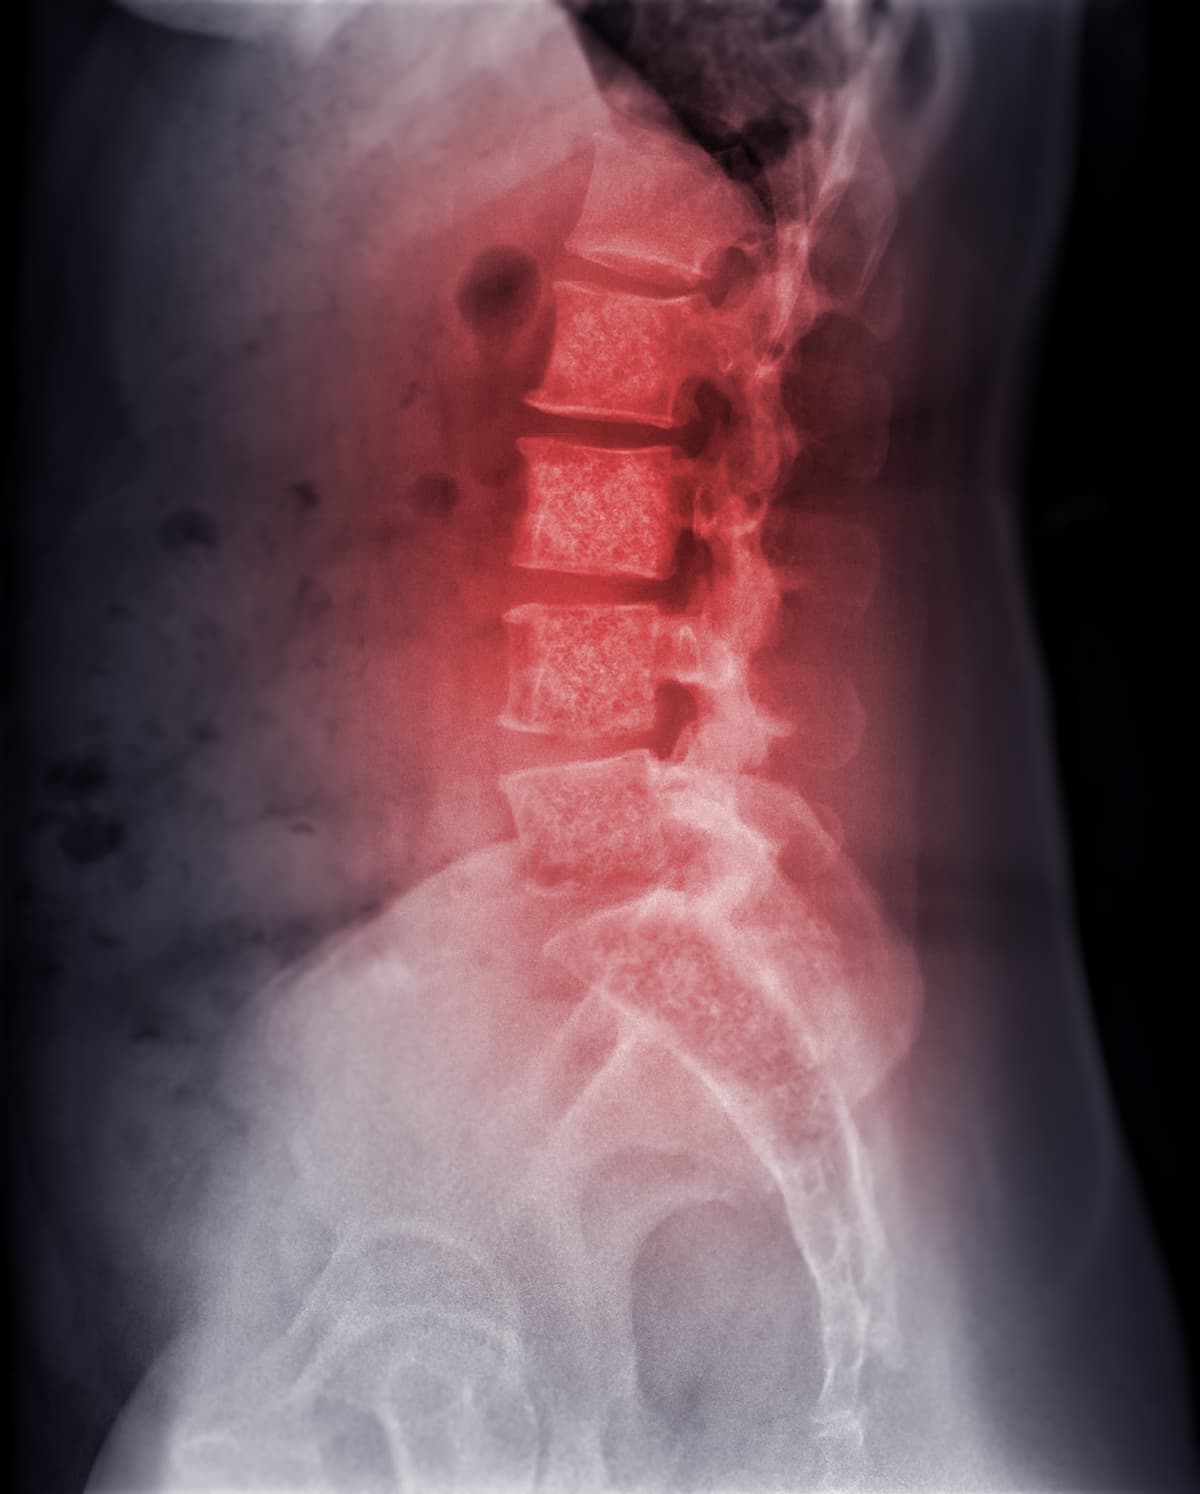

Stereotactic radiosurgery did not demonstrate superiority vs conventional external-beam radiotherapy (EBRT) in terms of 3-month pain response in patients with cancer who had spine metastases, although data may inform further investigation of spine radiosurgery in the oligometastatic setting, according to findings from the phase 2/3 NRG Oncology Radiation Therapy Oncology Group (RTOG) 0631 study (NCT00922974)1.

Investigators of the phase 2/3 NRG RTOG 0631 study randomly assigned patients 2:1 to receive treatment with stereotactic radiosurgery or conventional EBRT. In the radiosurgery group, patients received a single dose of 16 or 18 Gy to the margin target volume encompassing the involved vertebral bone, with prescription isodose line selections based on institutional preference. In the EBRT group, patients received a single dose of 8 Gy to the isocenter and delivered to the involved vertebral levels.